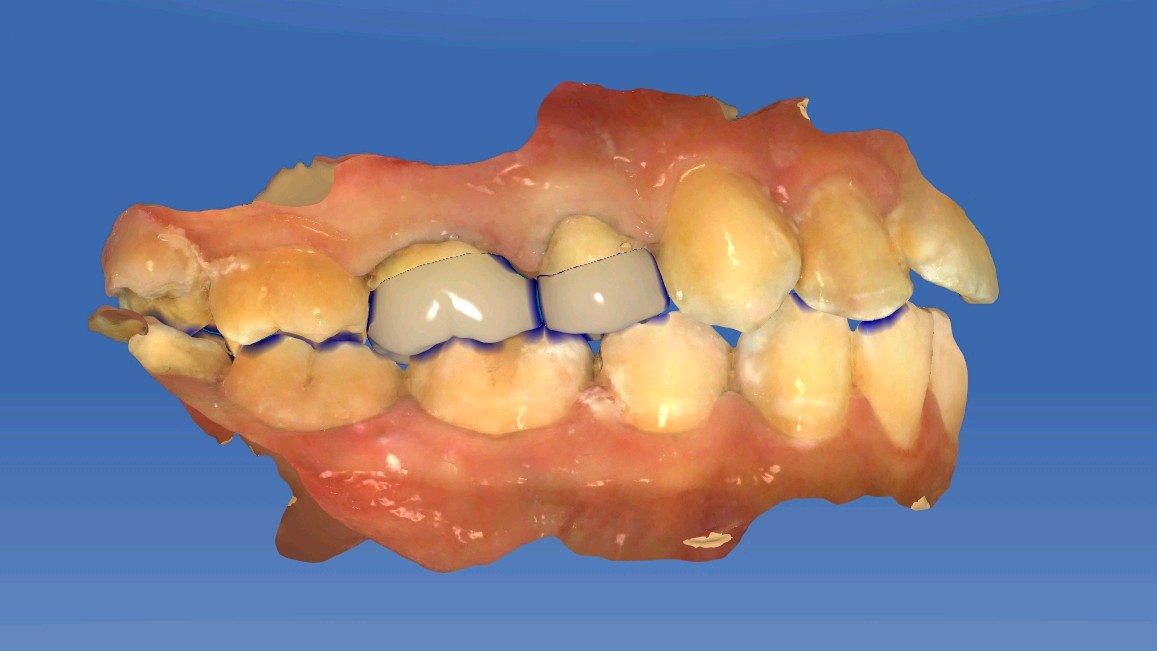

术中